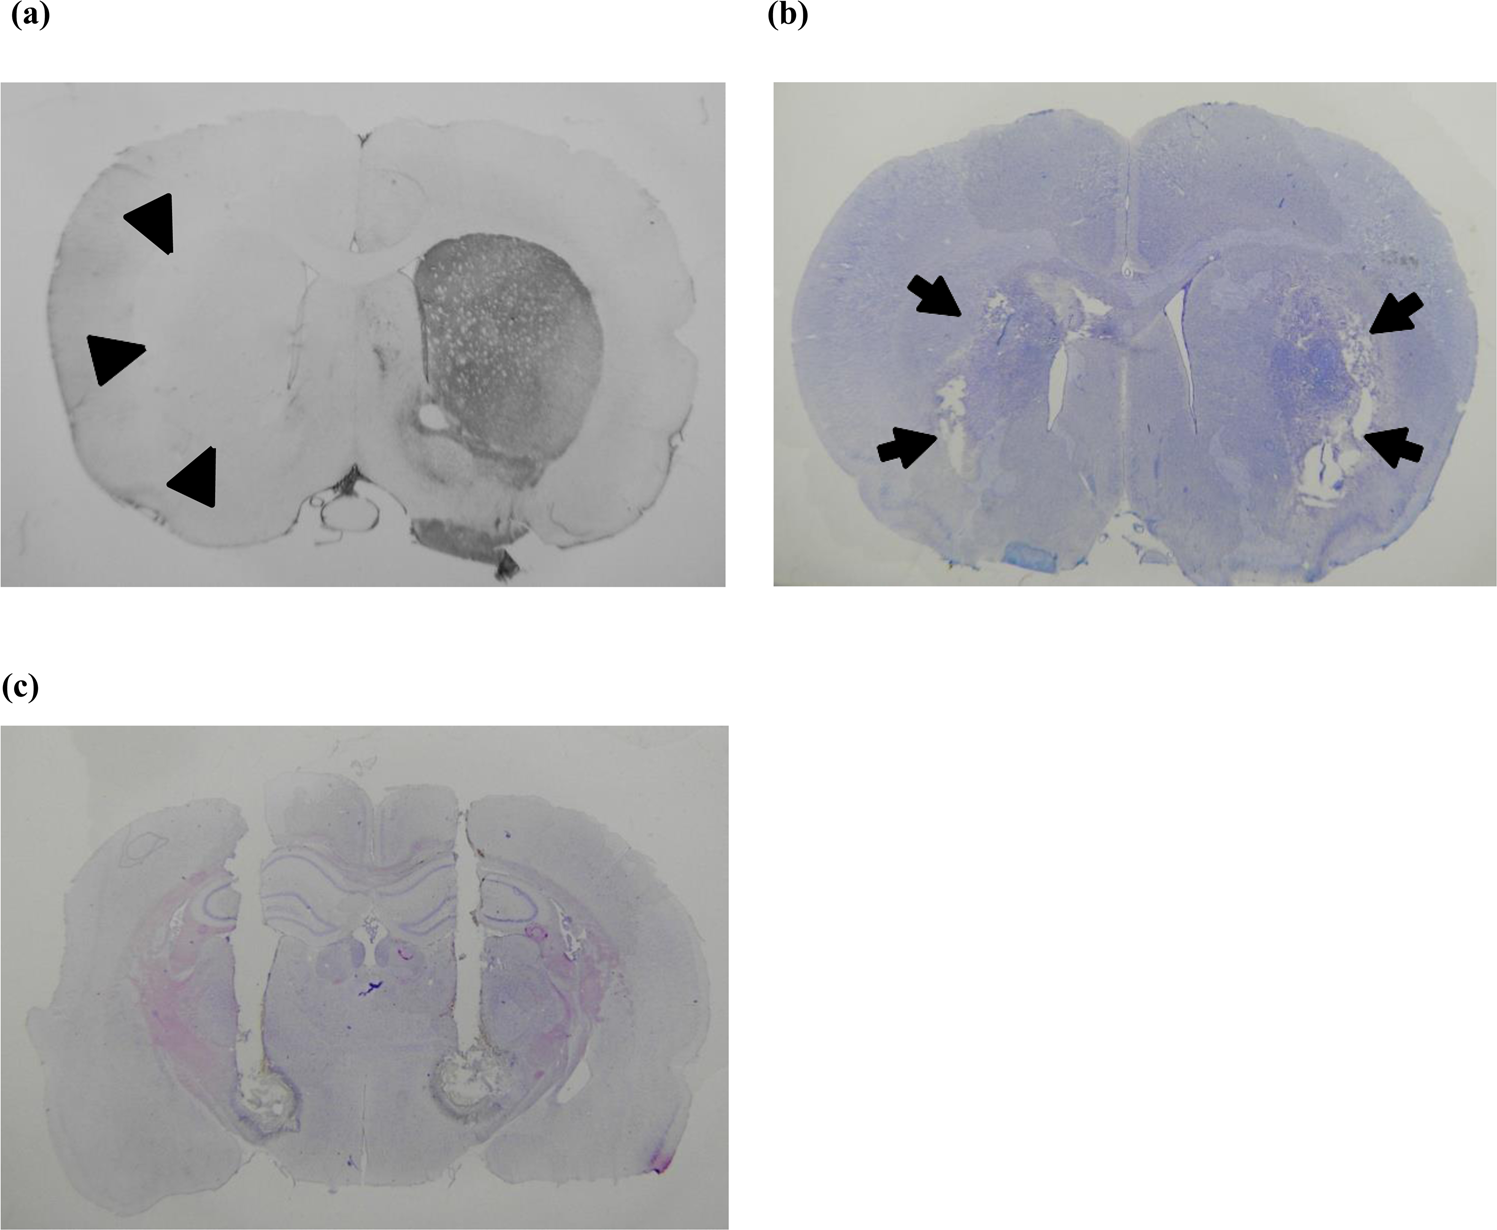

Figure 1

From: Hyperpolarization of the subthalamic nucleus alleviates hyperkinetic movement disorders

Histological verification of animal models of hyperkinetic movement. (a) Tyrosine hydroxylase immunohistochemistry showing unilateral deprivation of dopaminergic innervation of the striatum (arrowheads) in a parkinsonian rat with levodopa-induced dyskinesia. (b) Bilateral striatal lesions (arrows) in a rat with hyperkinesia after direct intrastriatal 3-NP injection shown by cresyl violet staining. (c) Cresyl violet staining showing trajectories of the combined microinjection cannula/stimulation electrode in the bilateral subthalamic region in a levodopa-induced dyskinesia parkinsonian rat.